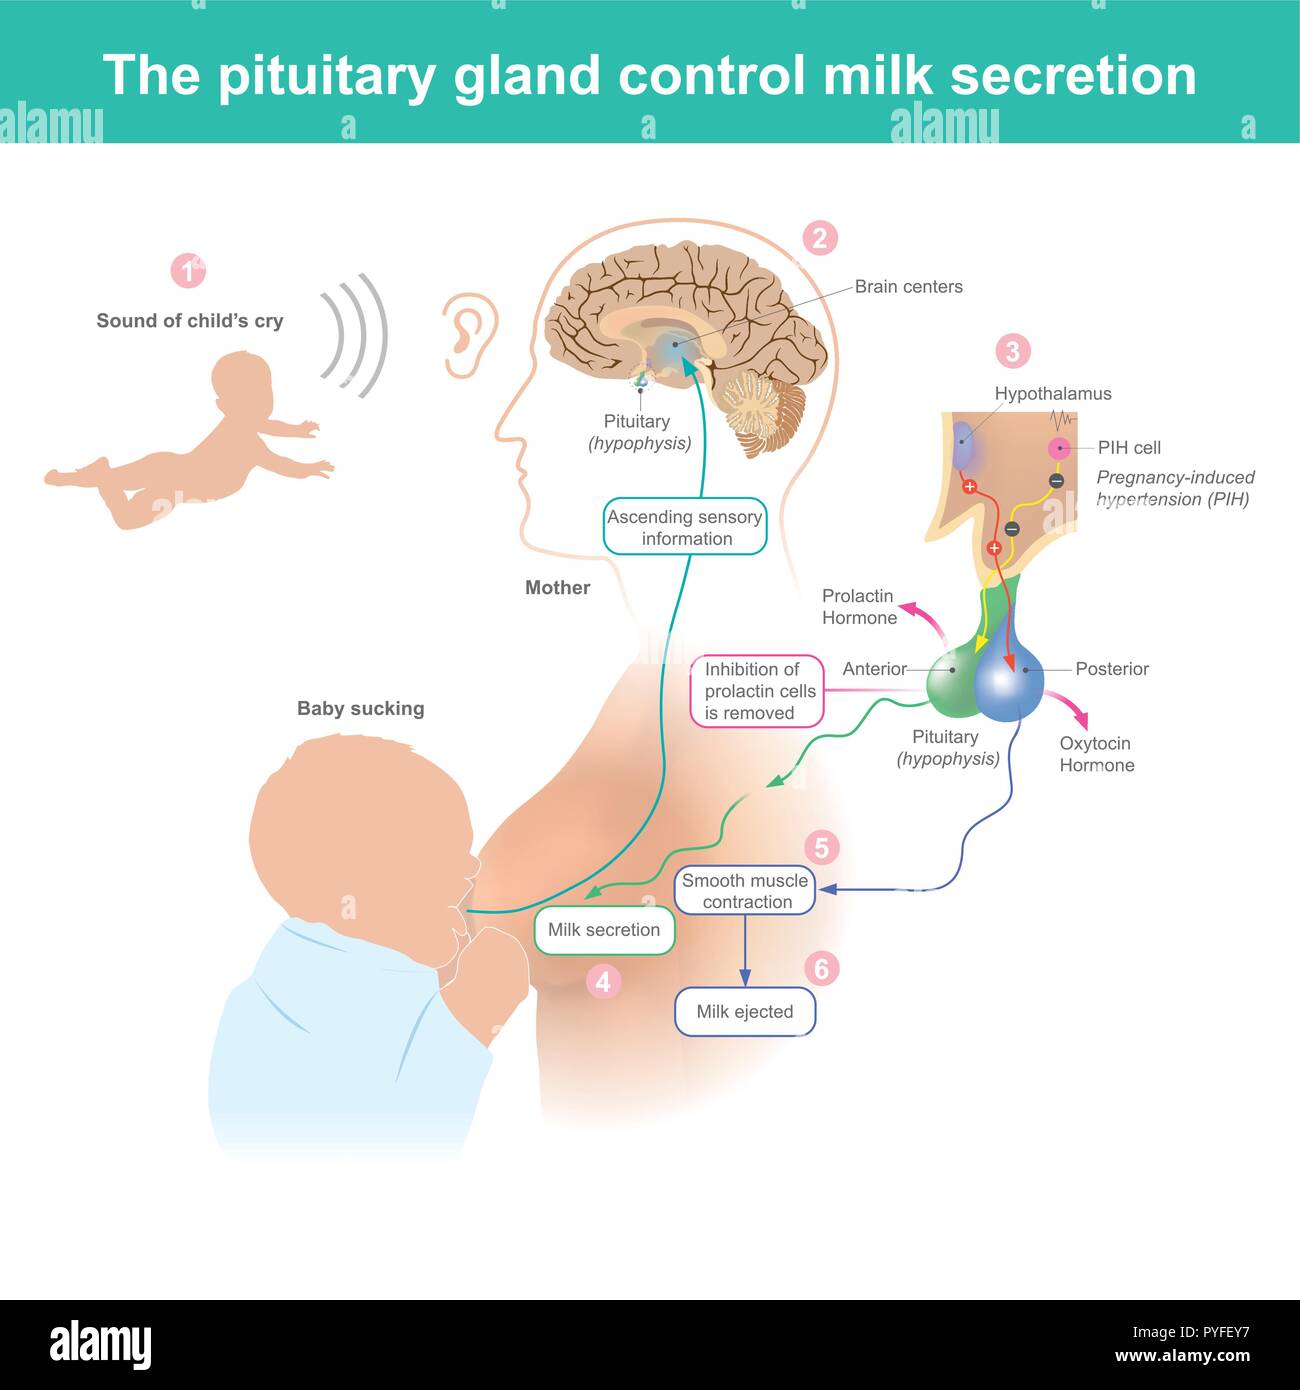

Quando la madre sente il bambino piangere. Il cervello attiva la gravidanza indotta da ipertensione cella (PIH) fornire latte di mammella. Illustrazione Vettorialehttps://www.alamy.it/image-license-details/?v=1https://www.alamy.it/quando-la-madre-sente-il-bambino-piangere-il-cervello-attiva-la-gravidanza-indotta-da-ipertensione-cella-pih-fornire-latte-di-mammella-image223461147.html

Quando la madre sente il bambino piangere. Il cervello attiva la gravidanza indotta da ipertensione cella (PIH) fornire latte di mammella. Illustrazione Vettorialehttps://www.alamy.it/image-license-details/?v=1https://www.alamy.it/quando-la-madre-sente-il-bambino-piangere-il-cervello-attiva-la-gravidanza-indotta-da-ipertensione-cella-pih-fornire-latte-di-mammella-image223461147.htmlRFPYFEY7–Quando la madre sente il bambino piangere. Il cervello attiva la gravidanza indotta da ipertensione cella (PIH) fornire latte di mammella.